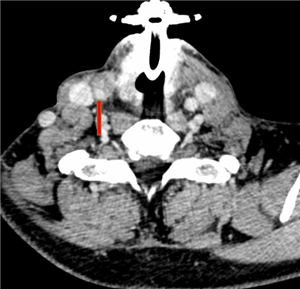

2:术后皮瓣重建的气管壁 图3:术后人工血管重建的颈总动脉

术前,陈飞教授团队联合麻醉科陈泓羊主治医师对患者病情进行了充分评估,就术中颈总动脉处理、脑部血供维持、气道重建策略、循环维持等关键点展开了多次讨论,制定了严密的手术方案。630日,手术成功切除了复发的甲状腺癌、受肿瘤侵犯包裹长达8cm的颈总动脉、部分颈内静脉、锁骨下静脉、椎静脉以及被侵犯的颈段气管右侧壁。肿瘤完整切除后,在颈动脉转流管有效保证术侧脑血管灌注的情况下,进行了人工血管置换重建颈总动脉,显微缝合修补/重建受累静脉,恢复了颅内外正常血供。最后,应用右侧胸肩峰动脉穿支皮瓣同期修复了颈段气管缺损,手术历时4小时。手术后患者安全返回耳鼻咽喉·头颈外科病房,接受了近1周治疗和悉心护理,现已顺利康复出院。